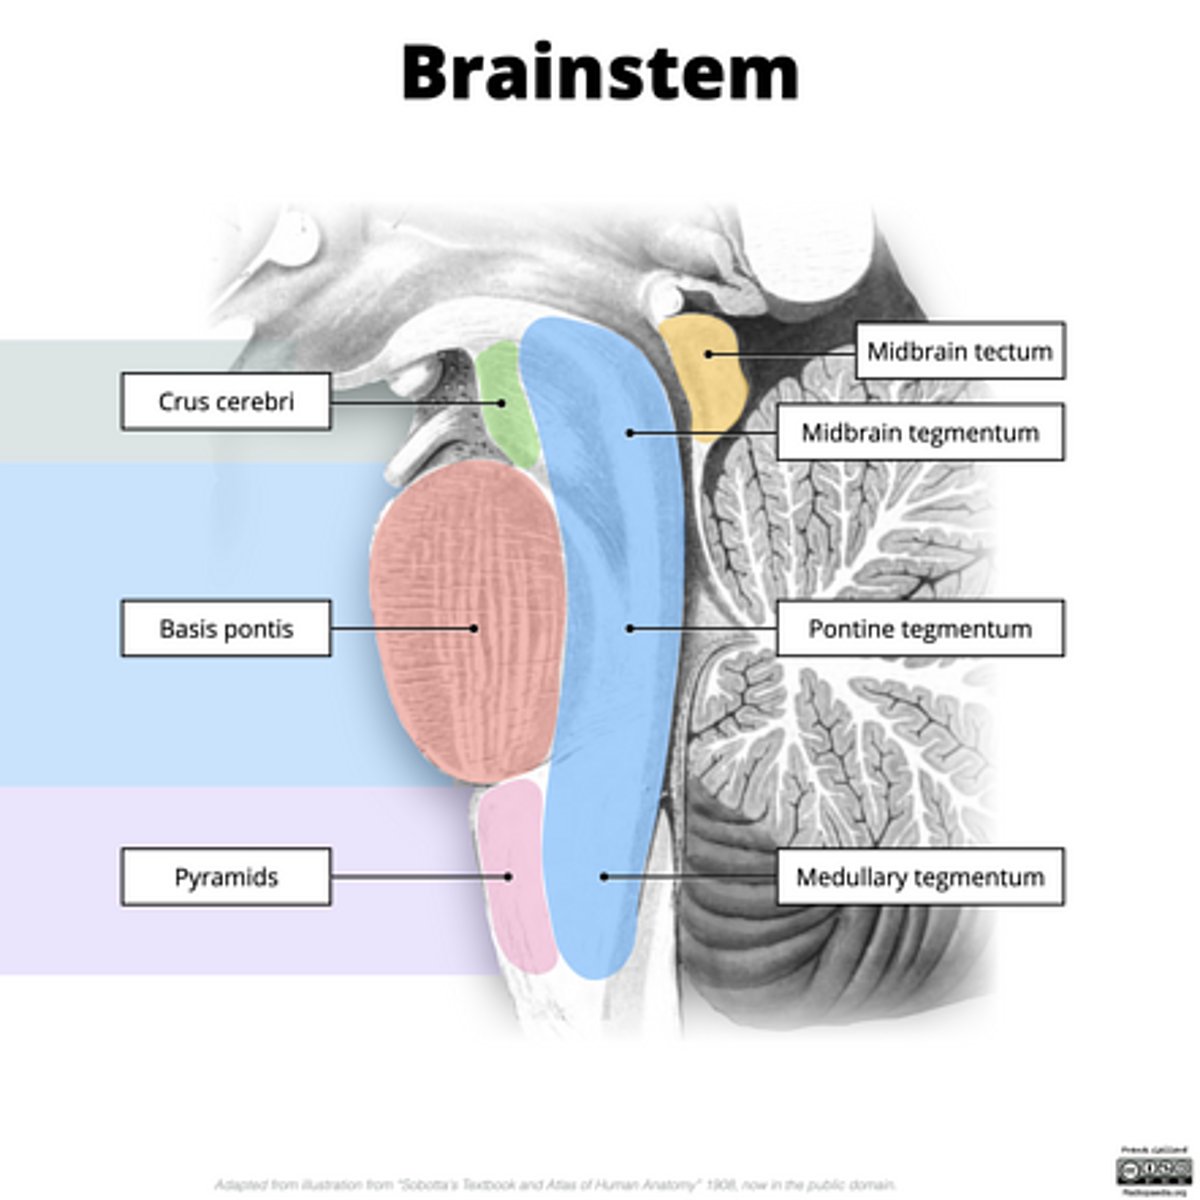

What are the structures of the brainstem?

1. mesencephalon (midbrain)

2. pons

3. medulla oblongata

What is the tectum?

roof of the midbrain

What is the tegmentum?

floor of midbrain

What are the fibers of the tegmentum?

ascending fibers

What is the crus cerebri?

part of the cerebral peduncles which contain descending tracts

What are the fibers of the crus cerebri?

descending fibers

image -- 5